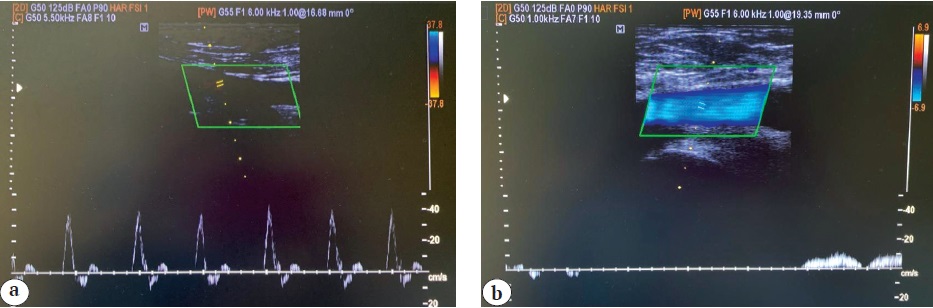

Three months after the discharge, the rivaroxaban dose was reduced to 10 mg/day, and after 6 months, the drug was discontinued; low doses of acetylsalicylic acid (50 mg/day) were prescribed. Data from repeated clinical examinations and control ultrasound studies demonstrated the preservation of the main blood flow through the damaged vessels (Fig. 5).

Fig. 5. Ultrasound duplex scanning (control study after 12 months): a — superficial femoral artery; b — common femoral vein